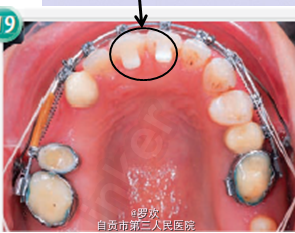

诊断:牙列缺损,凸面型,露龈笑 处理:上颌:内收上颌前牙,关闭磨牙缺失间隙,垂直向压低整个上颌牙列 下颌:内收下颌切牙,从而内收前突的唇。 拔除双侧下颌4,去除上颌局部固定桥,制作基牙的临时冠,,在上颌右侧3和5之间保留7.5mm的间隙供种植修复4,关闭所有间隙,种植钉内收和压低上颌前牙段,种植钉打在 颧牙槽嵴上,从种植钉上伸出悬臂簧用于压入上前牙以改善露龈笑,矫正结束后,在上下颌前牙段粘接舌侧丝固定保持